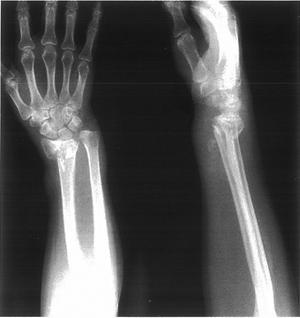

72歳の女性。歩行中に転倒して右手をついた。診療所で良好な整復を得て、ギプス固定を受けた。受傷直後の右上肢のエックス線写真を示す。この骨折について正しいのはどれか。

Colles骨折